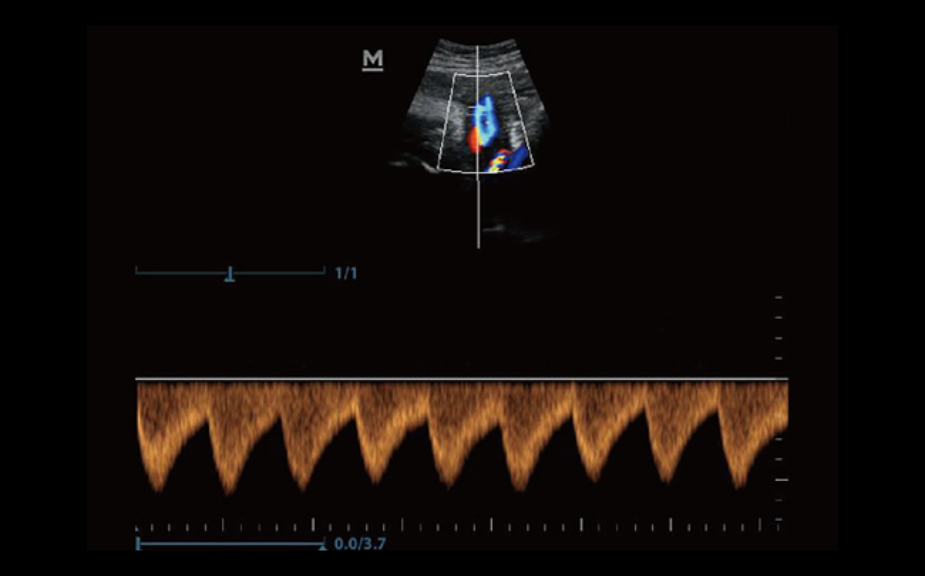

PSH? (Phase Shift Harmonic Imaging)

ImĂĄgenes de armĂłnicos purificados con desplazamiento de fase para una mejor resoluciĂłn de contrastes que proporciona imĂĄgenes mĂĄs nĂtidas con excelente resoluciĂłn y menos ruido.

iBeam?

Permite el uso de varios ĂĄngulos de exploraciĂłn para formar una sola imagen, lo que ofrece una mayor resoluciĂłn de contrastes y una mejor visualizaciĂłn.